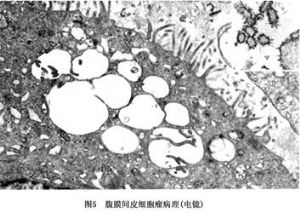

电镜技术特别是透射电镜技术,对诊断间皮肿瘤有极高的价值。其超微结构的特点是:间皮瘤的瘤细胞有众多的、细长的、刷样的微绒毛出现在瘤细胞的表面,但也可出现在细胞质内。但是在腺癌的微绒毛,数量较少,短棒状。间皮瘤的细胞内有巨大的细胞核、突出的核仁,中等量的线粒体被粗面内质网所包绕,常见糖原颗粒,成束的张力原纤维及细胞内空泡。滑面内质网不太发达。细胞外有基板,但多数不太完整。细胞间有连接,也可见桥粒。这些超微结构特点,主要见于上皮细胞性间皮瘤或混合性间皮瘤中。而纤维性间皮瘤,超微结构类似成纤维细胞,在梭形的瘤细胞中,有丰富的粗面内质网,偶见细胞间的微小腔隙以及微绒毛(图5)。

电镜技术特别是透射电镜技术,对诊断间皮肿瘤有极高的价值。其超微结构的特点是:间皮瘤的瘤细胞有众多的、细长的、刷样的微绒毛出现在瘤细胞的表面,但也可出现在细胞质内。但是在腺癌的微绒毛,数量较少,短棒状。间皮瘤的细胞内有巨大的细胞核、突出的核仁,中等量的线粒体被粗面内质网所包绕,常见糖原颗粒,成束的张力原纤维及细胞内空泡。滑面内质网不太发达。细胞外有基板,但多数不太完整。细胞间有连接,也可见桥粒。这些超微结构特点,主要见于上皮细胞性间皮瘤或混合性间皮瘤中。而纤维性间皮瘤,超微结构类似成纤维细胞,在梭形的瘤细胞中,有丰富的粗面内质网,偶见细胞间的微小腔隙以及微绒毛(图5)。

间皮瘤细胞电镜及酶组化特征:间皮瘤主要由上皮样细胞(epithelioid cell,EC),纤维母细胞样细胞(fibroblast-like cell,FLC),中间型细胞(interim cell,IC)及原始间叶细胞(primary mesenchymal cell,PMC)4种细胞组成。EC以丰富的微绒毛为特点,细胞表面有细长的微绒毛,其长径与宽径比例达10∶1~15∶1,这远远大于其他腺癌的比例,几个瘤细胞间围绕呈窦样隙,其内有许多细长的微绒毛交错在一起,FLC中粗面型内质网较多。EC脱氢酶及氧化酶活性较高,而水解酶活性较低。FLC细胞酶活性则与EC相反。这可能与两种类型细胞的功能活性不同有关。